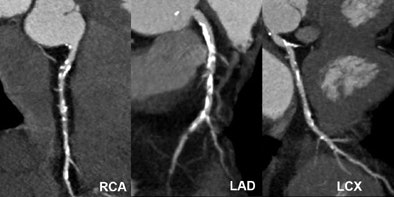

![]() |

| Significant calcified stenosis of the RCA and LAD, both correctly diagnosed with dual-source CT coronary angiography; and nonsignificant stenosis of the LCX. |